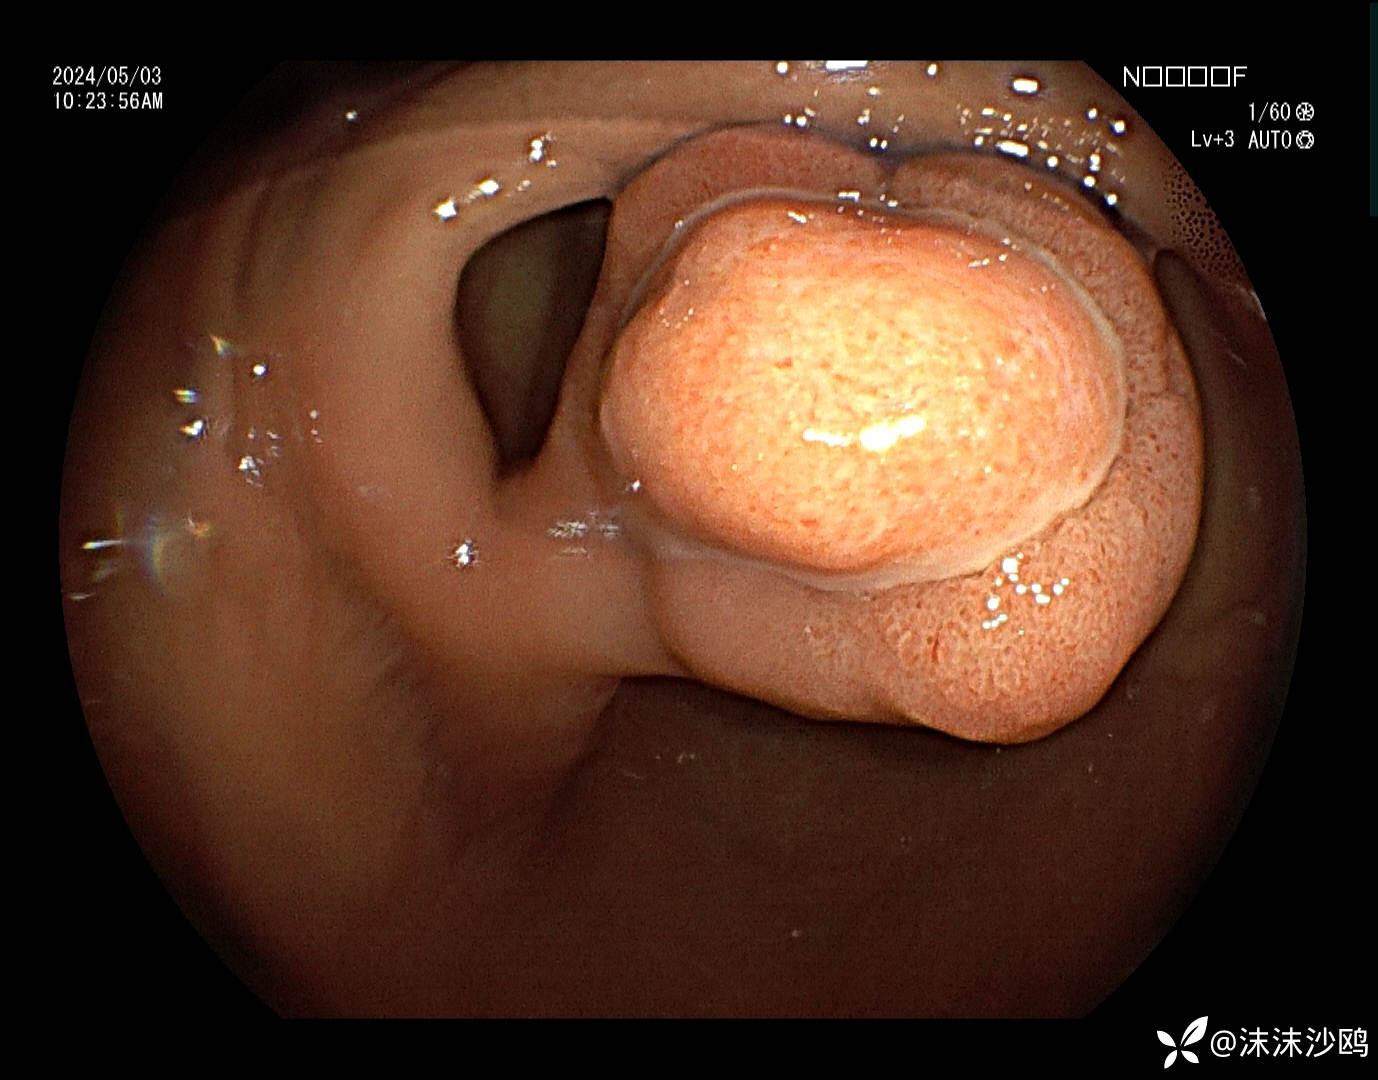

窦体交界近胃角前壁见一较大带蒂隆起性病灶,头端大小直径约2.5cm可见分叶结构,中央隆起跟边缘隆起的表面结构明显不同且有分界,沿分界线走向可见溃疡覆白苔。大致看上去就像一颗水煮蛋剥掉一部分蛋清露出蛋黄的感觉。

蒂部直径约1cm,凹陷见连续性溃疡,局部可见类似红色再生上皮?

倒镜病灶背面